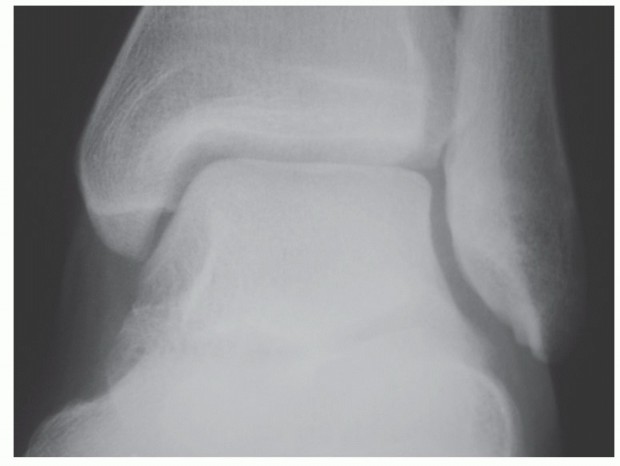

SURGICAL MANAGEMENT Preoperative Planning Imaging studies are reviewed. Physical examination should be done t…